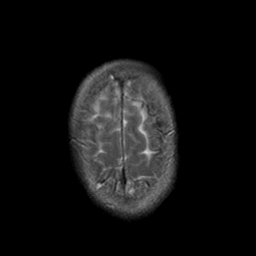

Stroke:T2-weighted MR #2 -- Slice #22

[Home][Help][Clinical] Slice 22